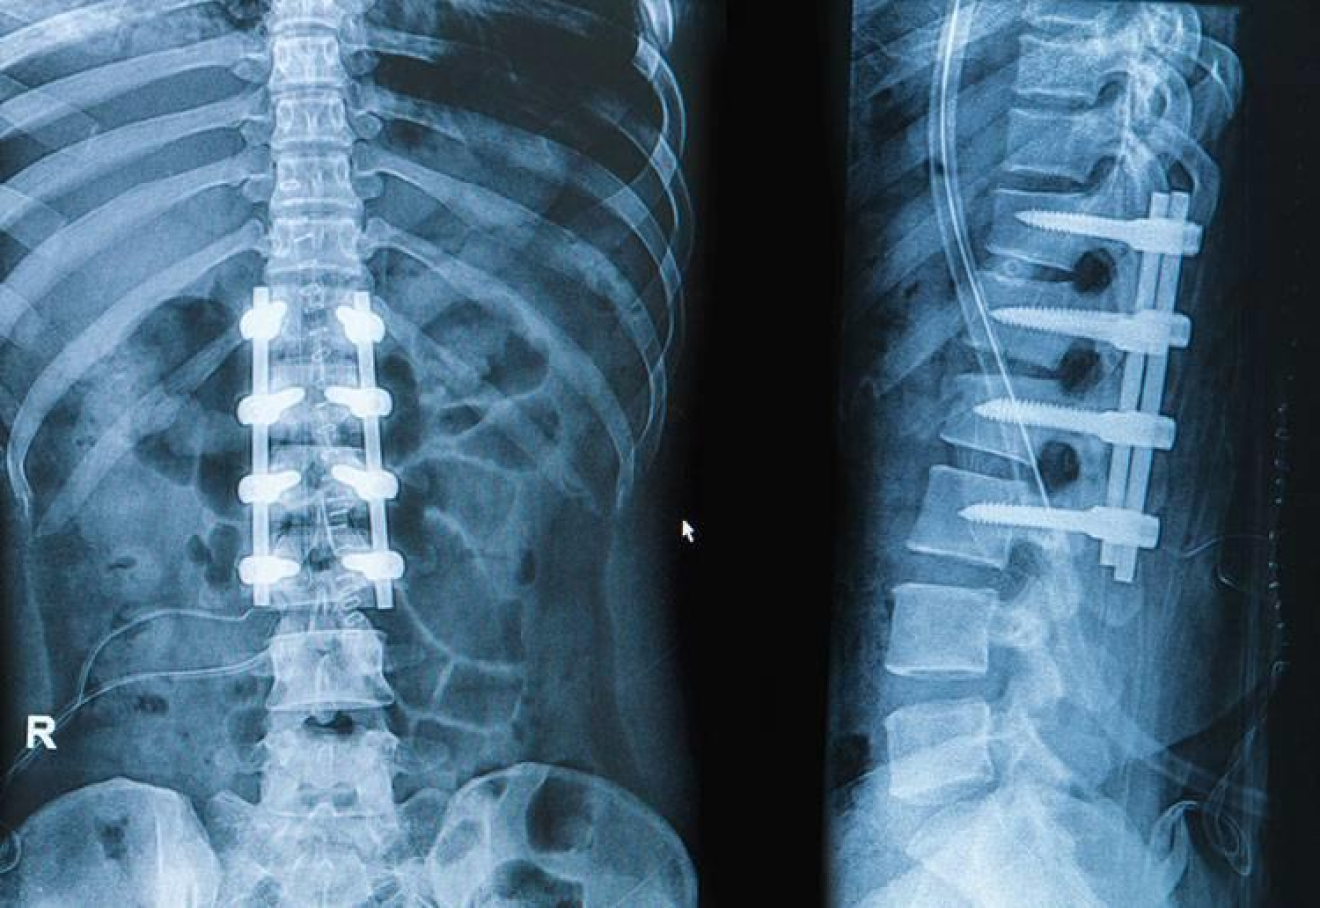

The DISCSEEL Procedure vs. Spinal Fusion

For decades, physicians have been recommending spinal fusions to patients, only for them to fail. These life-altering procedures have lead to some of the highest percentage of surgical failures and opioid dependency among surgical patients.

It was the high failure that lead to the creation of the DISCSEEL Procedure. So how do the two procedures compare to each other?

Here are some facts:

- In over 40% of patients that receive a spinal fusion, the fusion does not address the long term source of the pain.

- At least 1/3 of all spinal fusion patients need a second or third fusion of their spine within ten years.

- The DISCSEEL Procedure has been successful in permanently relieving back pain in 70% of patients that had a previous failed spinal procedure, such as a spinal fusion